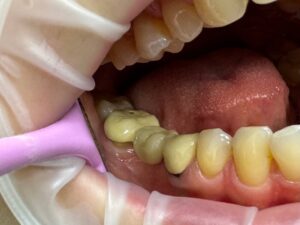

Замена металлокерамической коронки на более эстетичную и современную циркониевую коронку с керамическим нанесением. Стоимость работы - 22000р

В этой ситуации наглядно показано одно из важных отличий ДО и ПОСЛЕ — это просвечивание металлического края у металлокерамики в области десны ДО и полностью светлые зубы ПОСЛЕ. Для этого и были проведены работы — чтобы все зубы были светлыми и эстетичными.

Изготовлена комбинированная вкладка, затем циркониевая коронка с керамическим нанесением. В работу также вошла временная коронка. Стоимость работы - 38000р